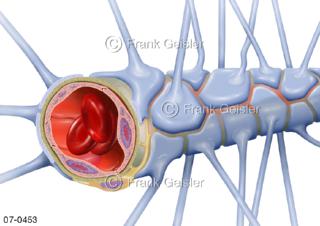

Bildergalerie Herz, Blutkreislauf

Bilder zu Herz, ein muskuläres Hohlorgan, das den menschlichen Körper durch rhythmische Kontraktionen mit Blut versorgt und dadurch die Durchblutung der Organe sichert, das Kreislaufsystem zeigt den Transport von arteriellem sowie venösem Blut durch das kardiovaskuläre System (Herz-Kreislauf-System), bestehend aus Blutgefäßen, Lymphgefäßen und dem Herz